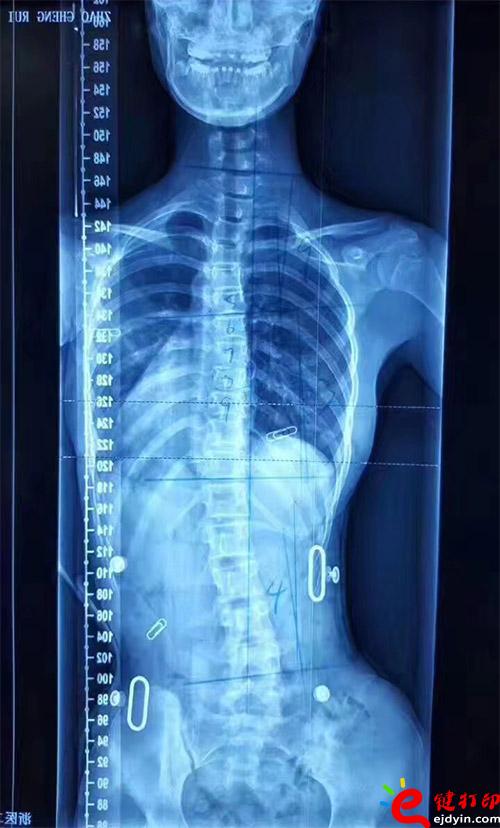

在脊柱側(cè)彎患者中,僅有10%的青少年特發(fā)性脊柱側(cè)彎患者最終需要手術(shù)治療,90%的患者可以保守治療和積極觀察。非手術(shù)治療中公認(rèn)最主要和可靠的方式是用矯形支具治療。像上圖這樣的案例就可以通過(guò)矯形器治療。每個(gè)人的畸形不一樣,就需要像3D打印這樣可定制又便宜的技術(shù)幫助。